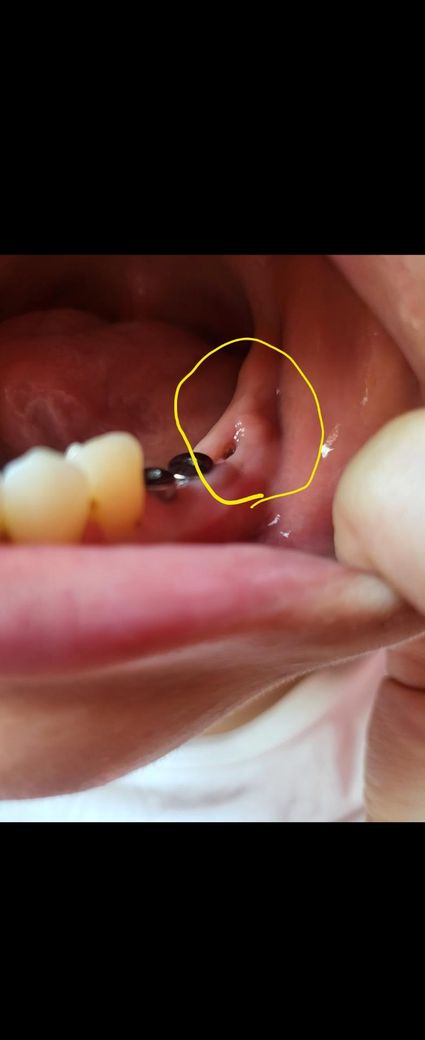

뼈이식 후 한달째인데 염증이 생긴걸까요?

왼쪽 맨 아래 어금니 뼈이식한지 한달되었어요

오늘 이빨닦다가 보니 뼈이식한 주변쪽에 볼록한 느낌이 들어서 염증이 생긴건지 궁금해서 여쭤봅니다 ㅠㅠ

아픈건 하나도 없고 만져도 통증은 없어요

뼈이식 후 한달째인데 염증이 생긴 것으로 보이지는 않고 잘 회복되는 과정으로 판단 됩니다.

잇몸 수술을 하고 나면 잇몸 수술을 한 부위에 잇몸이 들어가거나 할 수 있습니다. 크게 문제가 되거나 하진 않을 것으로 생각됩니다. 잇몸이 아무는 데는 이 주 정도의 시간이 걸리며 그 이전에는 잇몸이 자극되지 않도록 하는 것이 좋습니다. 잇몸이 자극되는 출혈이 되고 치유가 늦어질 수 있기 때문입니다.

사진에 보이는건 염증이 아니고 잇몸이 눌려서 물집같은게 잡힌거 같습니다. 치과에 가셔서 확인후 터트리거나 그냥 두셔도 될것같습니다.